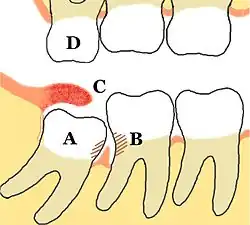

A = Retinierter Weisheitszahn 48 mit mesialer Karies;

B = distale Karies am Zahn 47, dazwischen Gingivitis;

C = entzündete, künstliche Zahnfleischtasche;

D = Elongierter Zahn 18

Die Position des dritten Molaren in Bezug zur Okklusionsebene des zweiten Molaren und zum Abstand zwischen dem Ramus mandibulae (aufsteigender Unterkieferast) und der distalen Seite des zweiten Molaren haben Glenn J. Pell und G. Thaddeus Gregory klassifiziert.[4][5] Daneben gibt es die Klassifikation nach G. B. Winter,[6] die von W. H. Archer[7] und G. O. Kruger[8] modifiziert wurde.[9]